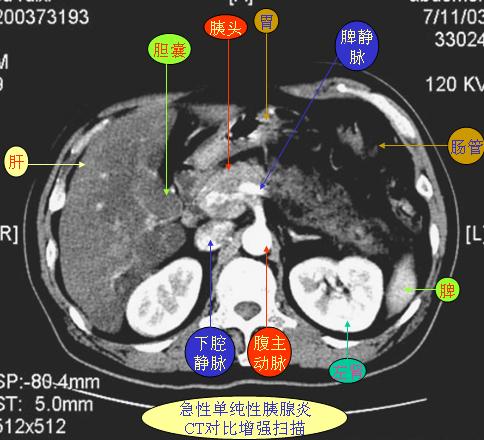

腹部ct解剖与基本病变